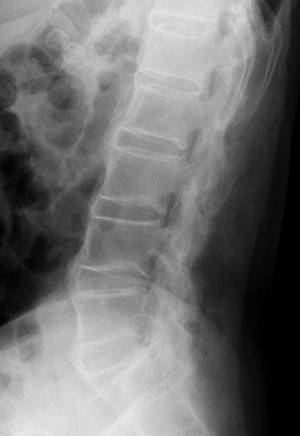

希少難病である強直性脊椎炎は、病変部位では靭帯と骨との付着部位に炎症・骨化が起こり(図1)、疼痛、運動制限等がみられ、重症例では、体軸関節の強直をきたして日常生活能力の著しい低下をもたらします。FPP003は幅広い炎症性疾患に関与するタンパク質IL-17Aに対する抗体を誘導するペプチド治療ワクチンであり、強直性脊椎炎に代表される体軸性脊椎関節炎の新規治療選択肢となることが期待されます。

図1:強直性脊椎炎の脊椎レントゲン写真